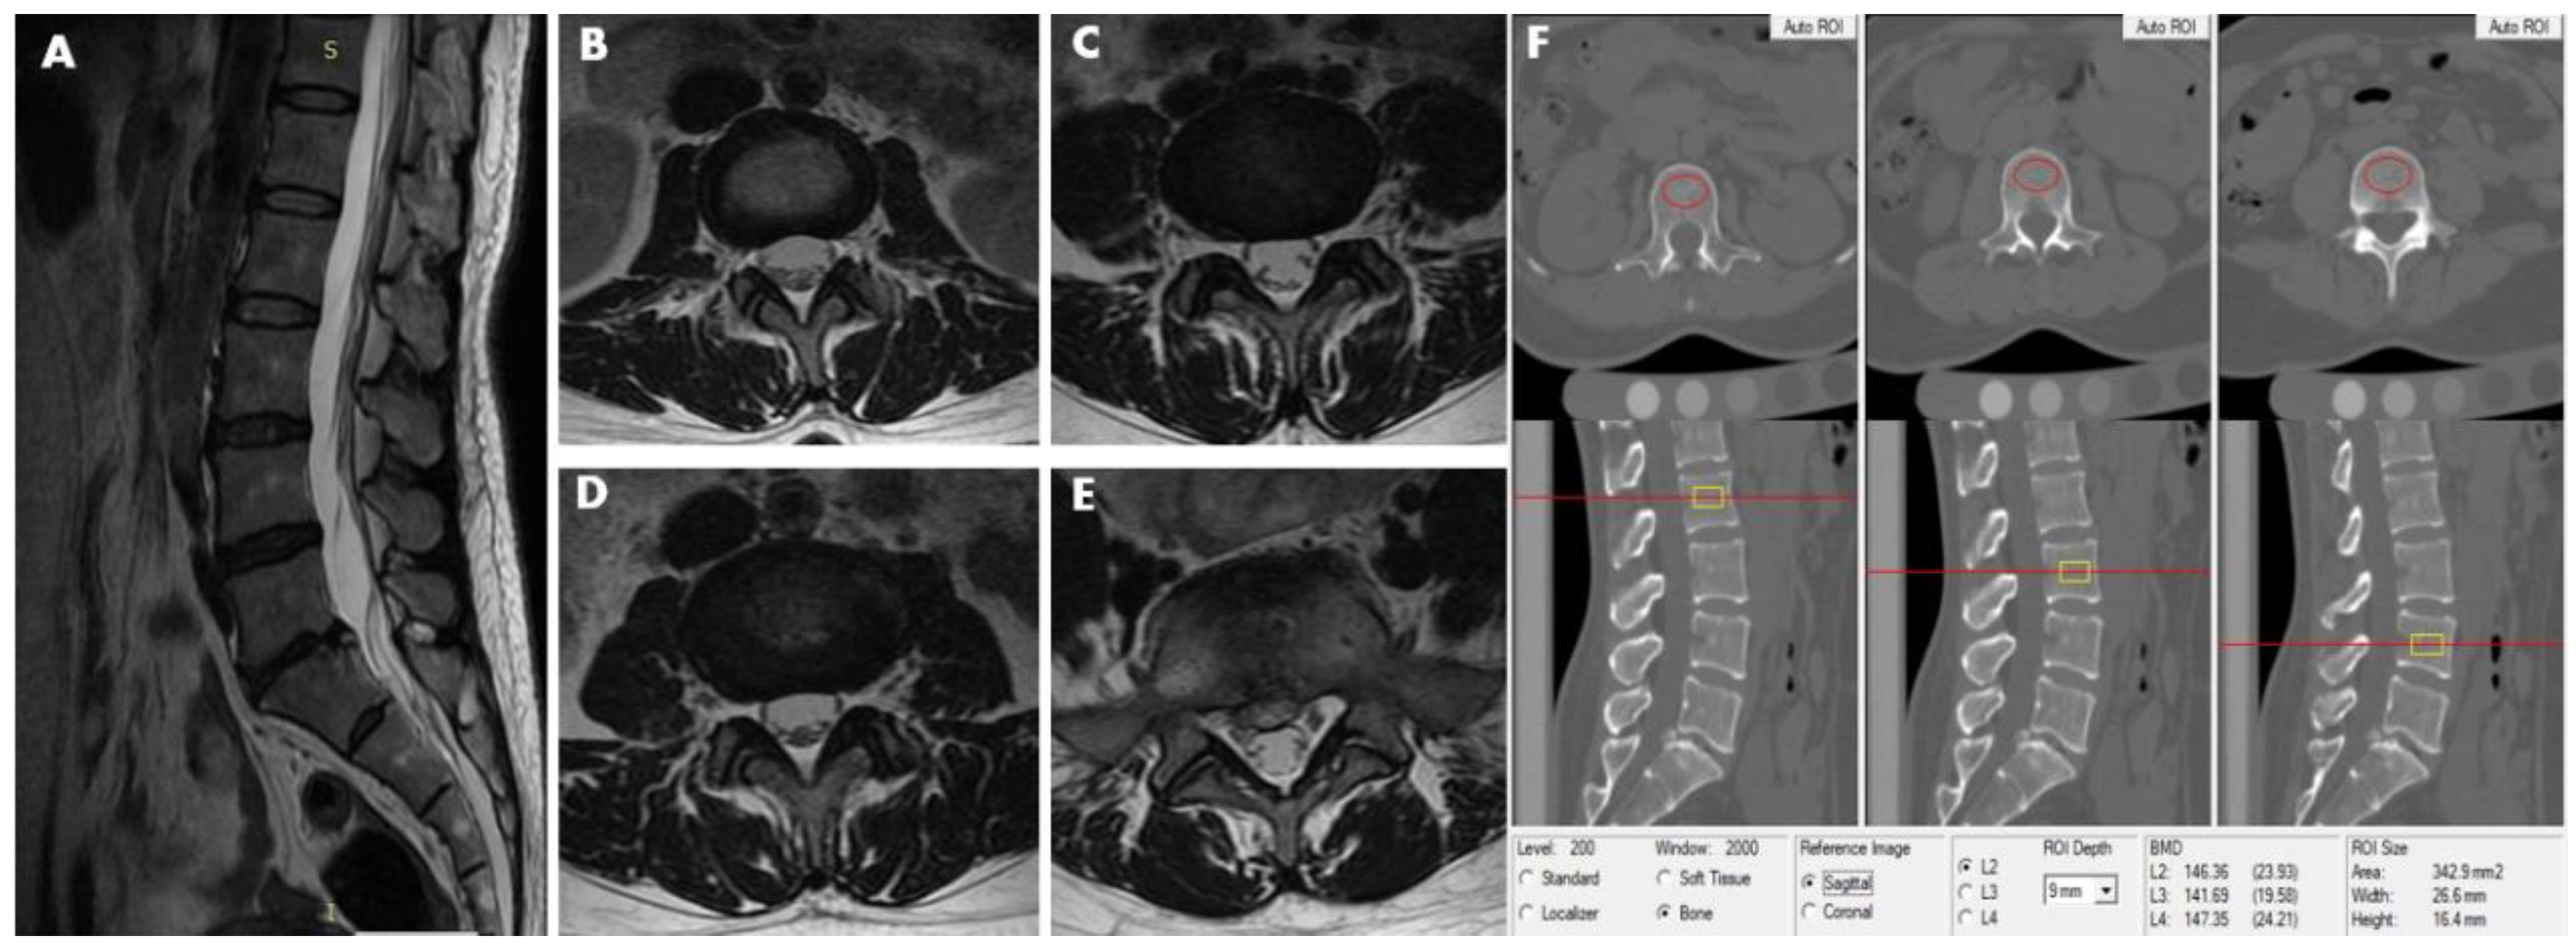

Figure 2.

This 40-year-old female participant was assigned to the LDH group and subgroup 1. MRI (T2-weighted image) revealed lumbar disc herniation condition from L2–3 to L5–S1disc. (A) Sagittal image revealed lumbar disk herniation in the level of L5–S1. (B) L2–3 axial image shows no abnormality in disc morphology. (C) L3–4 axial image showns no abnormality in disc morphology. (D) Also, the L4–5 axial image shows no abnormality in disc morphology. (E) L5–S1 axial image show focal protrusion at the central canal zone with a high-intensity zone (HIZ). (F) The measurements of L2, L3, and L4 vertebral trabecular volumetric bone mineral density (Trab.vBMD) are shown; the BMD of L2, L3, and L4 is 146.36 mg/cm3, 141.69 mg/cm3 and 147.35 mg/cm3, respectively. The average lumbar Trab.vBMD is 145.13 mg/cm3.